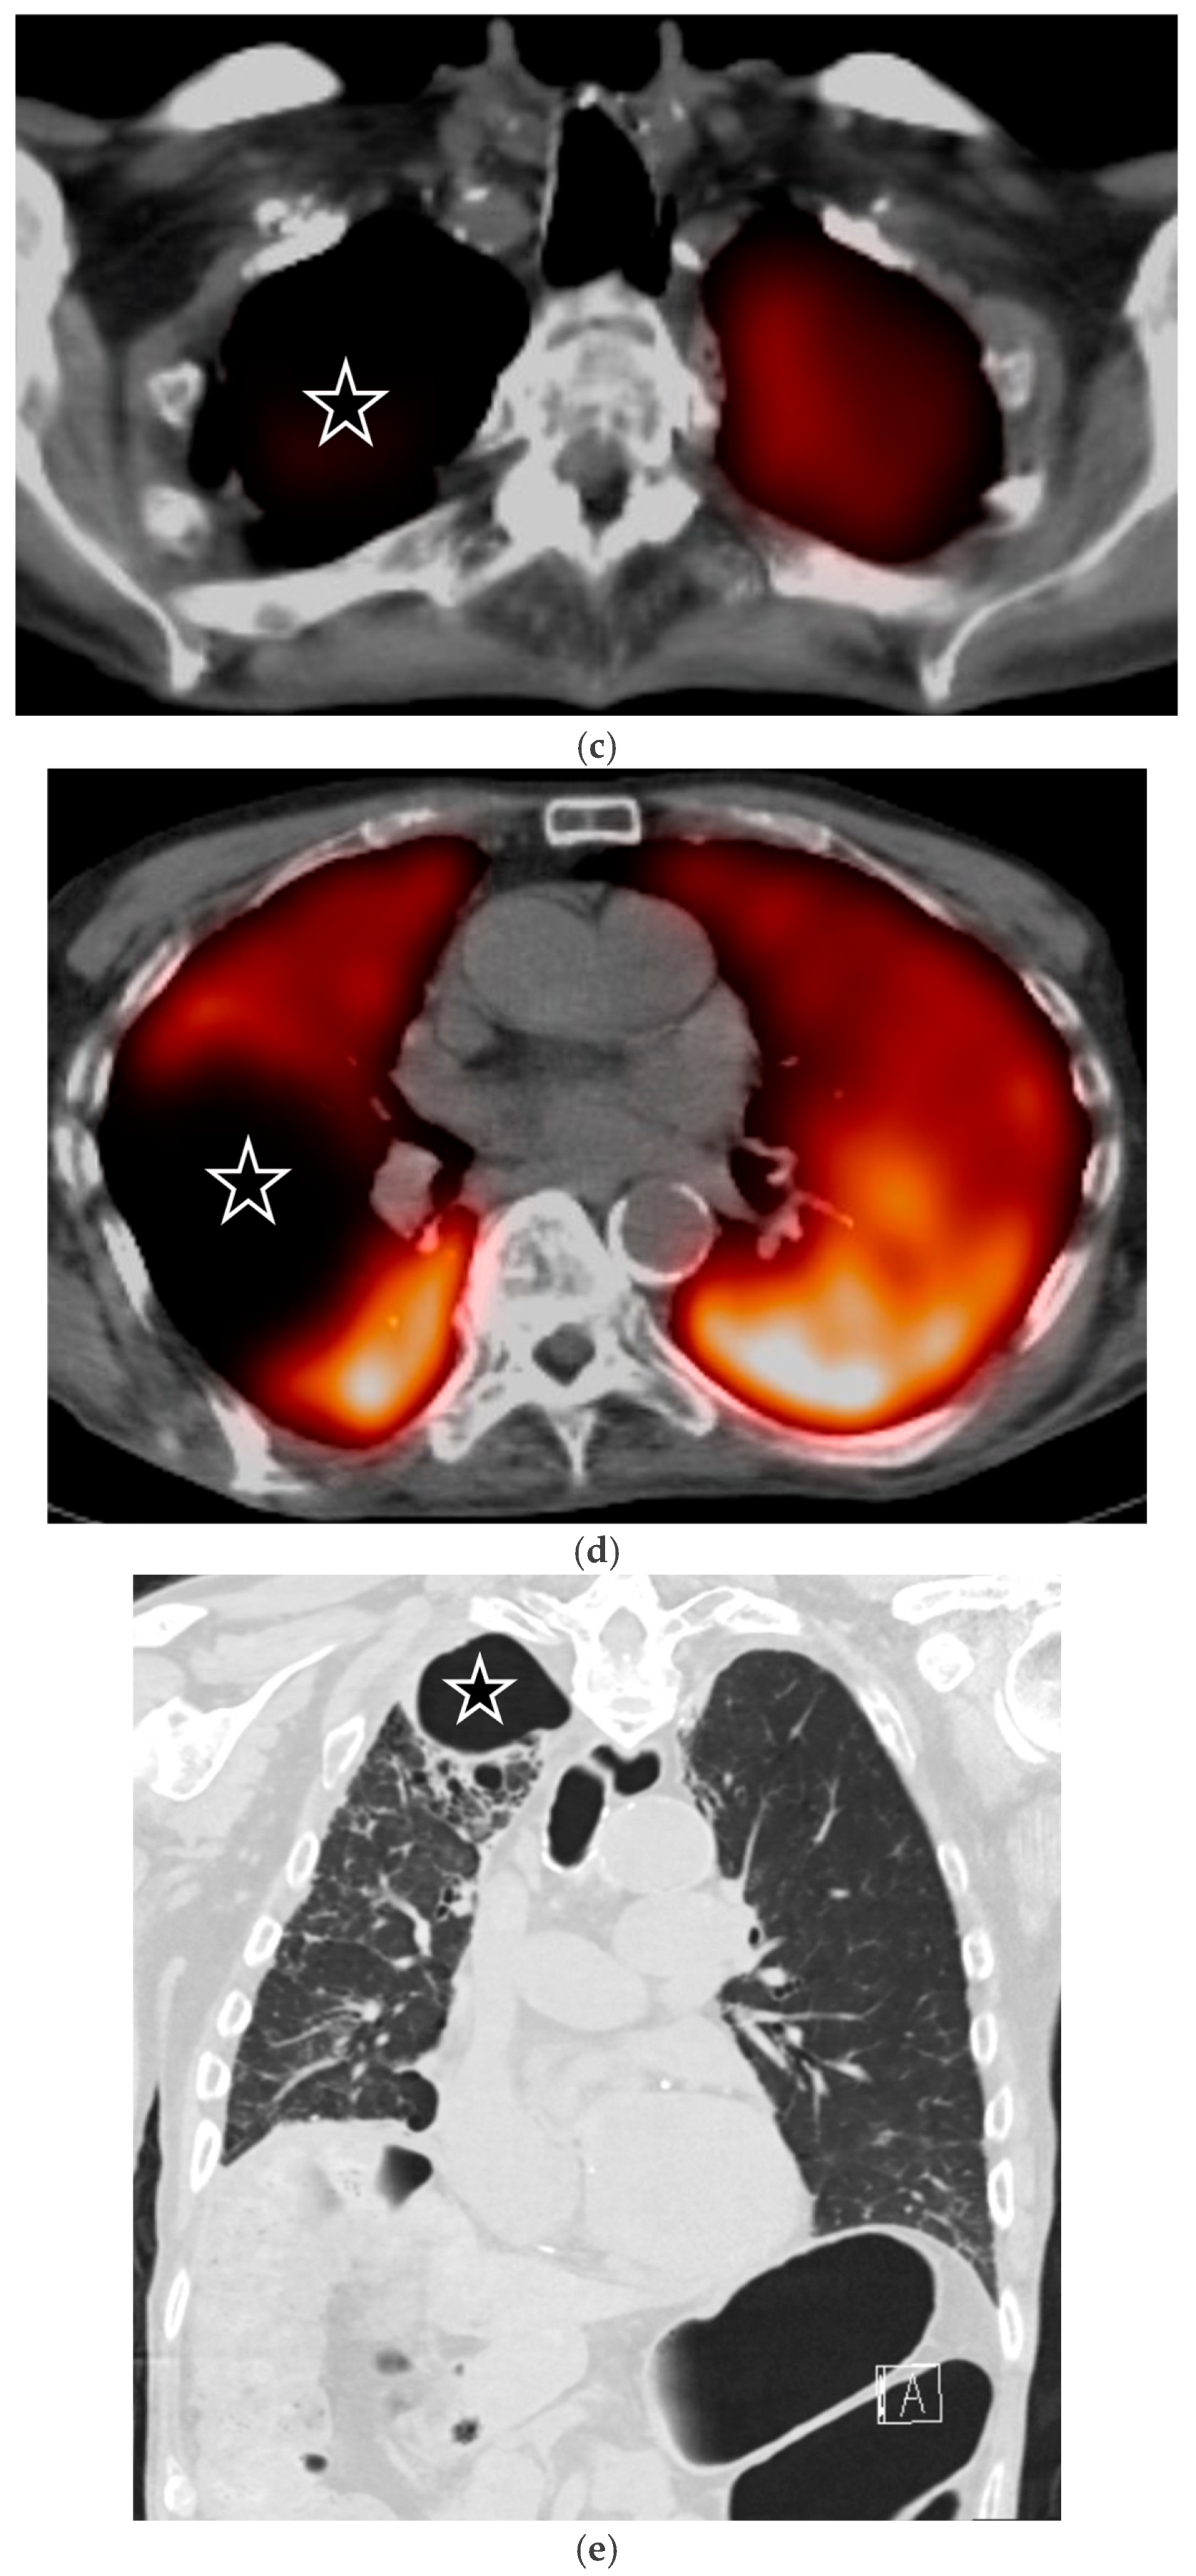

5.1.2. COVID-19 Pneumonia

5.1.3. Pneumocystis jirovecii Pneumonia (PJP)